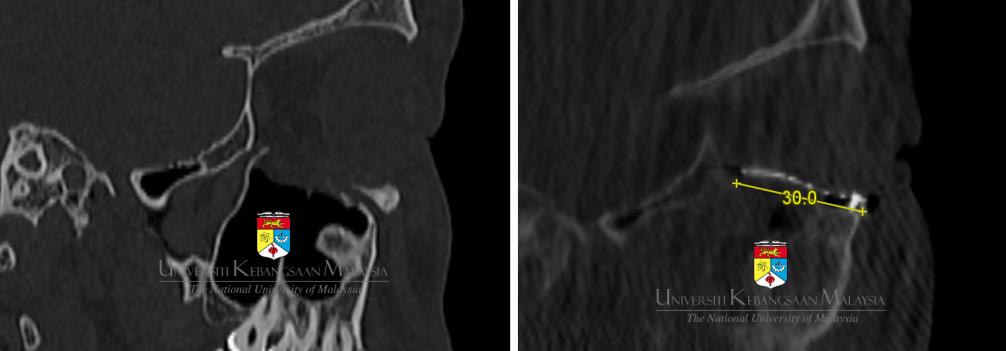

As a tertiary referral center, our services are supported with state-of-the-art medical and surgical equipment. Our center is well-recognized in Malaysia for treating complex maxillofacial conditions such as osteoradionecrosis, medication-related osteonecrosis of the jawbones, orthognathic surgery, and especially computer-assisted or computer-aided oral and maxillofacial surgery.

Among the achievements of the department is the successful performance of the ‘osteo-odonto-kerato-prosthesis’, which enabled a corneal blind patient to regain sight. Additionally, we successfully conducted Malaysia’s first computer-generated, fully customized, patient-specific maxillofacial implants using both PEEK and titanium. In Malaysia, we also pioneered the use of intraoperative computed tomography scan for use in major maxillofacial and orbital trauma. Working closely with industry leaders such as Brainlab (M) Sdn Bhd, Depuy Synthes, KLS Martin, and many others, our center also successfully performed the very first navigational surgery for a panfacial fracture, including bilateral severe orbital fractures.

Computer-assisted planning and surgical methods are now routine for all patients with severe midfacial, orbital, and/or panfacial fractures, as well as for jaw reconstruction following tumor resection and increasingly being use for the orthognathic surgery procedures. To date, more than 120 patients who sustained orbital blowout fracture have benefited from this advanced and individualized treatment protocol. We have also extended our computer-assisted surgical services for the management of jaw tumors through collaboration with Peking University School of Stomatology.